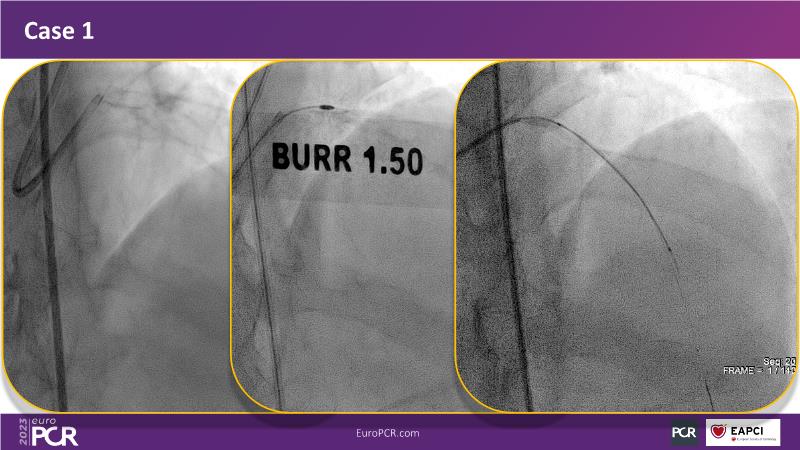

In this session, review the evolution in the use of IVL over the last few years, with a widening of the indications, observe that OCT can underestimate the number and depth of calcium fractured induced by IVL, or see that the technique is safe and effective in high-risk patients, including ACS patients, as demonstrated in real-world registries, among others!

- To understand how intravascular lithotripsy (IVL) in clinical practice has evolved over the last five years

- To evaluate the effects of IVL in different patterns of calcific coronary disease